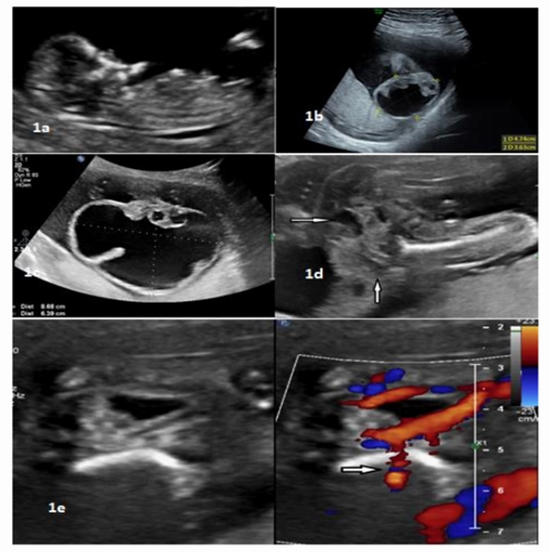

Ultrasonography and Magnetic Resonance Imaging in a Fetus with Sacrococcygeal Teratoma: A Case Report

Case Report: We present a case of large fast growing (86x63mm) mostly cystic SCT in a 27-year-old woman with 23 weeks of gestational age and normal first trimester ultrasound exam. The fetus was evaluated by both magnetic resonance imaging (MRI) and ultrasonography.

Conclusion:  Findings regarding tumor location, size, and content were similar for both sonography and MRI methods, though vascular pattern was detected with higher accuracy and more details by sonography. Meanwhile, MRI provided more appropriate information about tumor effects on surrounding tissue and conus location.